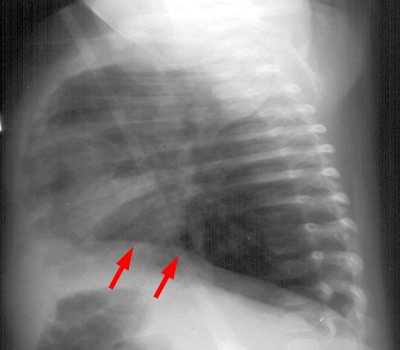

The bronchial inflammation results in areas of mucus plugging and atelectasis whereas other areas of the lung will demonstrate hyperinflation from air trapping. The overall lung volumes will be hyperinflated with an increase in the anterior retrosternal space and flattening of the diaphragms.

LAT CXR demonstrates flattening of the diaphragms. |